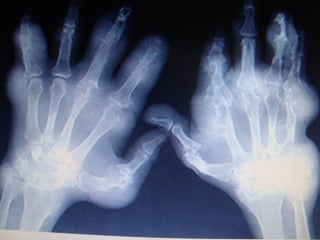

O Em poucos pacientes uma forma articular

destrutiva (artrite mutilante) pode se

desenvolver (Figura 3).

Figura 3 - Artrite destrutiva na DMTC, com

dedos em "telescópio" (de Robert M.Bennet,

UpToDate, 2007).